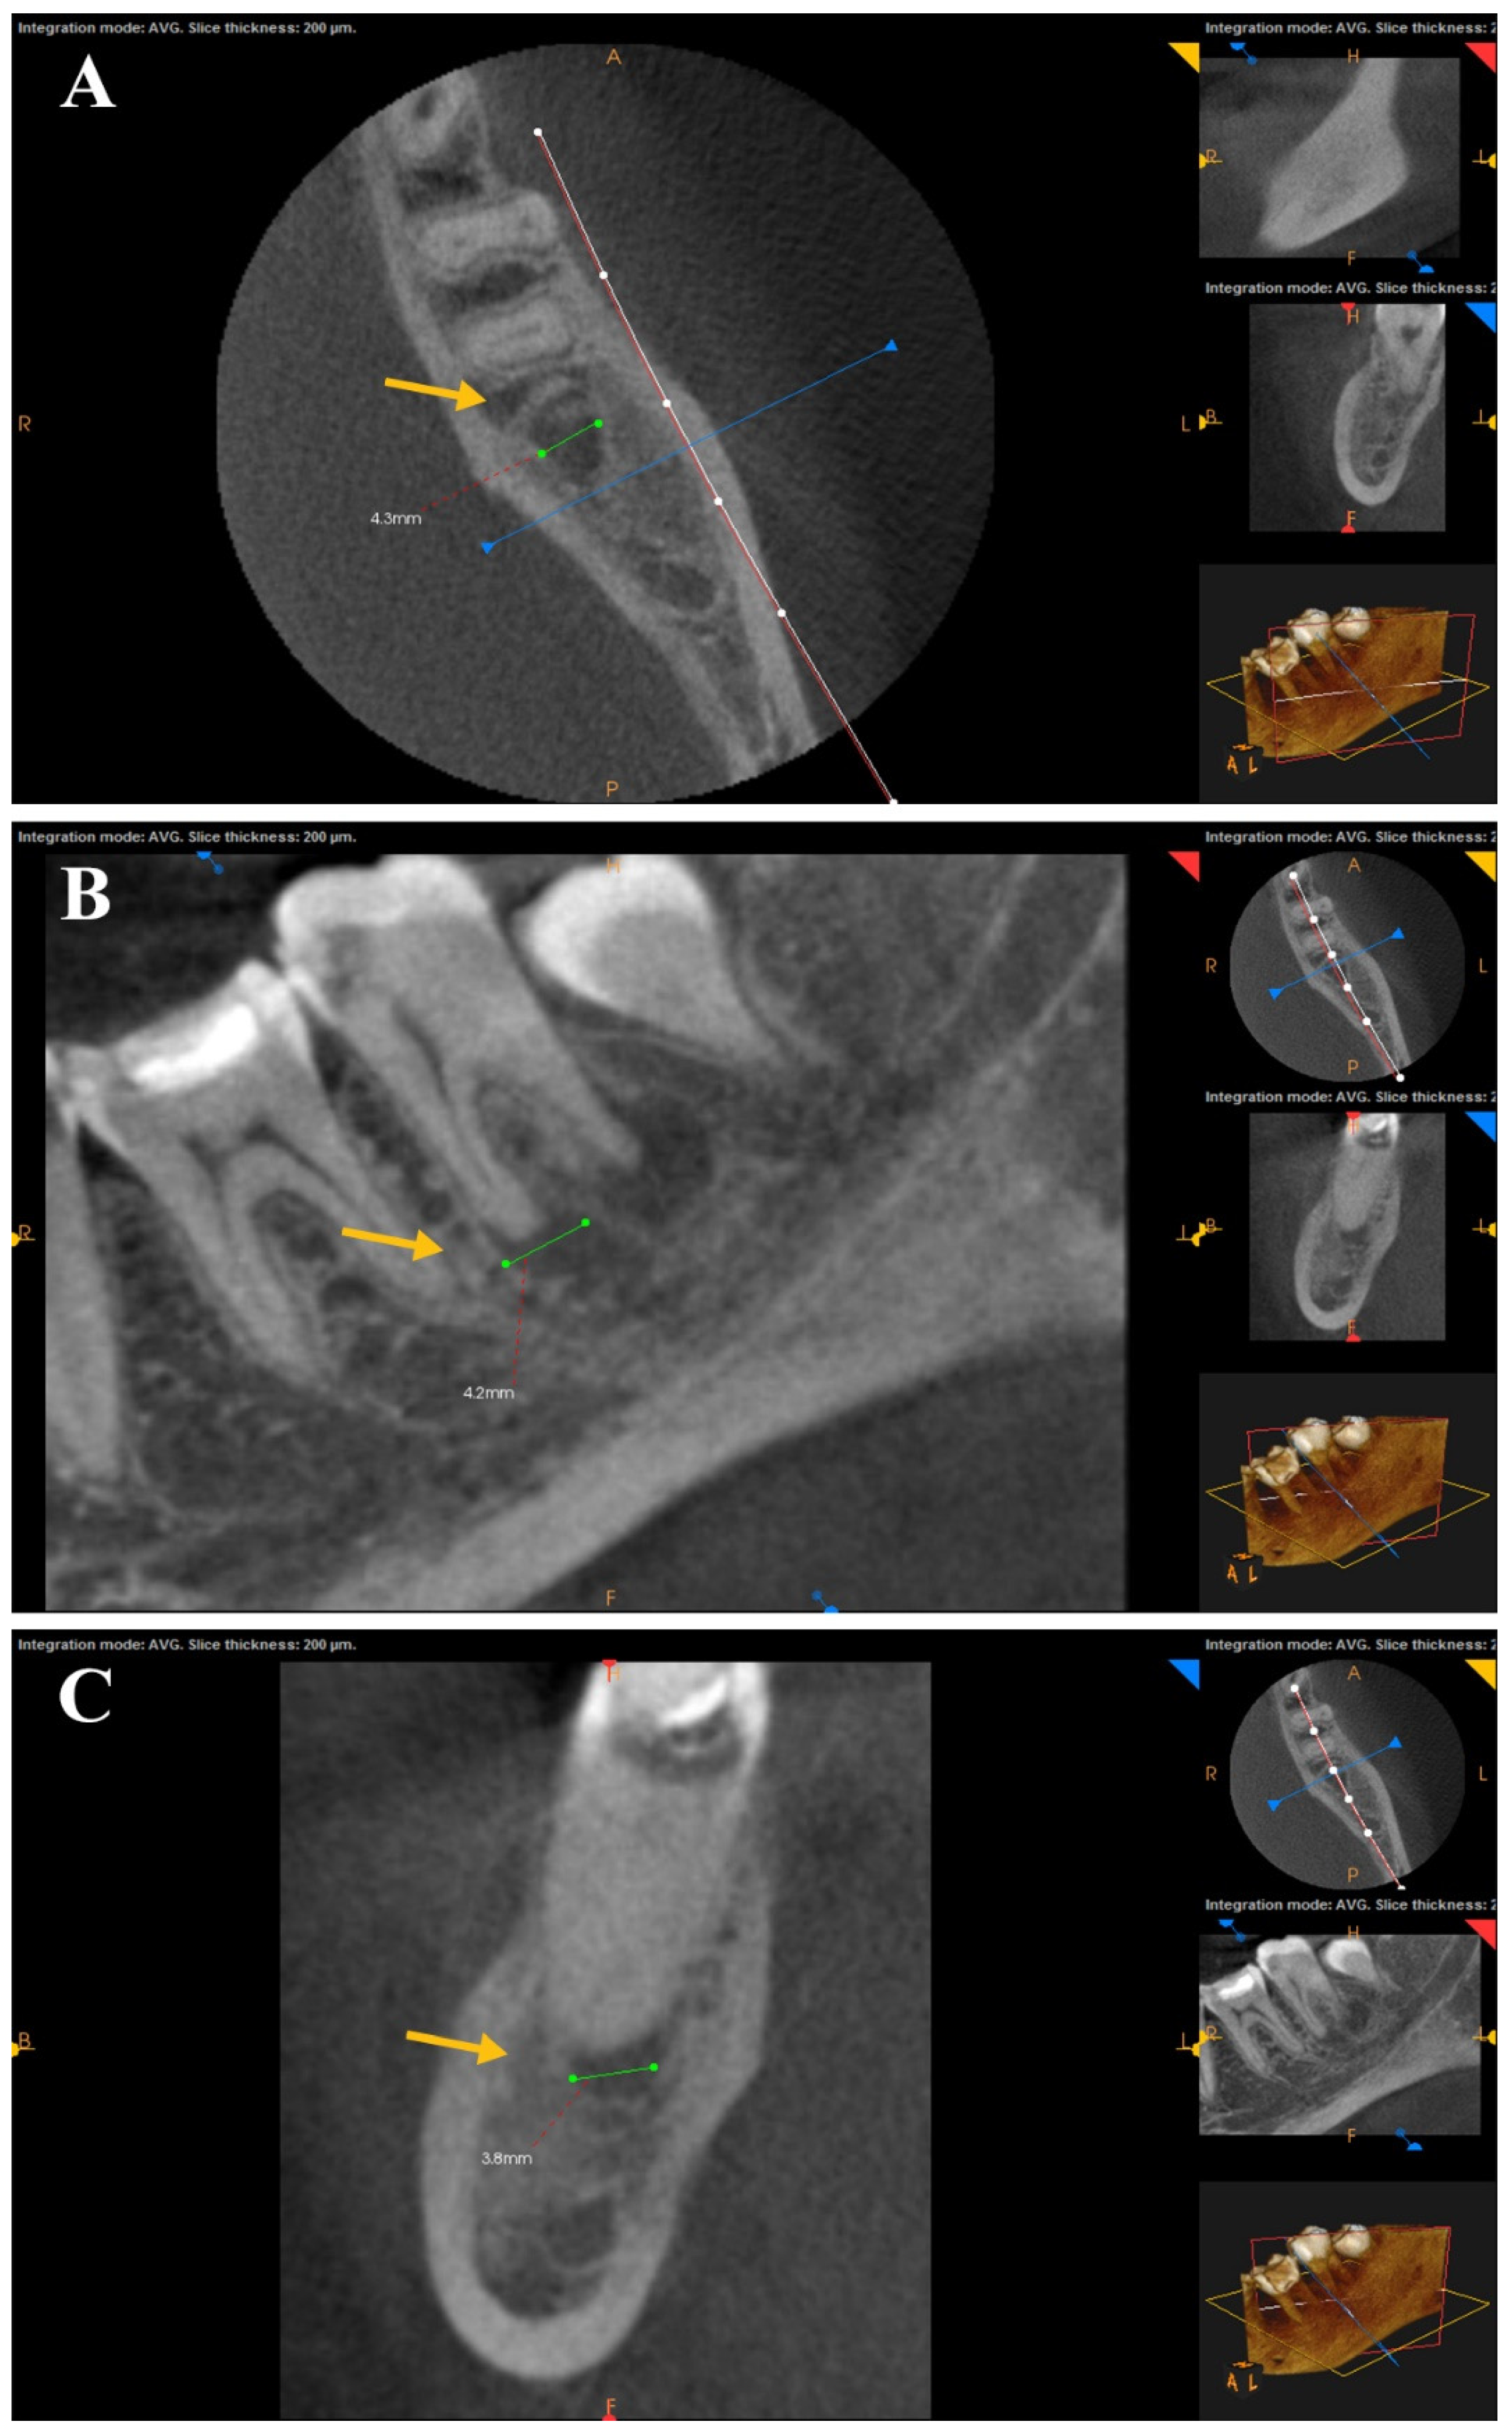

The clinical evaluation was conducted at a one-year follow-up visit for each patient, including spontaneous pain, sinus tract, swelling, mobility, periodontal probing depths greater than baseline, or sensitivity to percussion or palpation [17]. A post-operative CBCT image was obtained and compared to the pre-operative one to assess the impact of canal preparation of each file on the periapical lesion based on Estrela et al. [18] CBCT periapical index (CBCT PAI) to obtain three orthogonal linear measurements (bucco-lingual, mesio-distal, and diagonal) for each lesion (Figure 2). The largest measured diameter was used for scoring with the CBCT-PAI. Two independent examiners performed measurements on the digital CBCT images using the software measurement calipers; the measurements were blinded concerning group allocation. Discrepancies were resolved by repeat measurement and consensus resolution (ICC = 0.91). This semi-automated, computer-aided approach improved measurement reproducibility and minimized observer bias. Cortical bone expansion (E) and cortical bone destruction (D) were included in the scoring system as appropriate [17] (Table 2). If one of these conditions was found in the CBCT analysis, the variables E and D were added to each score.

Figure 2. CBCT scans show the axial (A), sagittal (B), and coronal (C) planes. The largest extension of the lesion (yellow arrow) determined the score in the CBCT PAI.